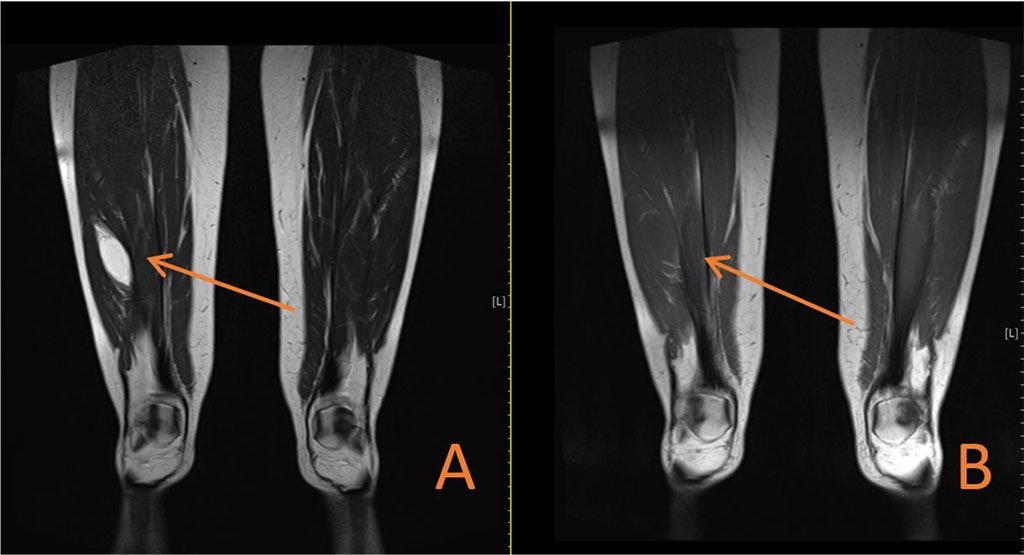

The patient came with laboratory tests and ultrasound results which were performed some time earlier. Laboratory investigation, including a complete blood count, prothrombin time C-reactive protein test showed no abnormalities. Ultrasound examination revealed a well-defined, oval-shaped area of reduced echo intensity within the muscle tissue. Further, more detailed imaging was planned. Magnetic resonance imaging (MRI) confirmed the presence of the tumor. The tumor measured about 6 cm in length, 2 cm in width, and 2 cm in sagittal diameter. It appeared hyperintense on T2-weighted images (Figure 2A, Figure 3A) and hypointense (resembling fluid) on T1-weighted images (Figure 2B, Figure 3B).

Figure 2. (A) Coronal MRI section showing high signal intensity on T2-weighted imaging in oval-shaped lesion in the Vastus lateralis. (B) Coronal MRI section showing low signal intensity on T1-weighted imaging in oval-shaped lesion in the Vastus lateralis.